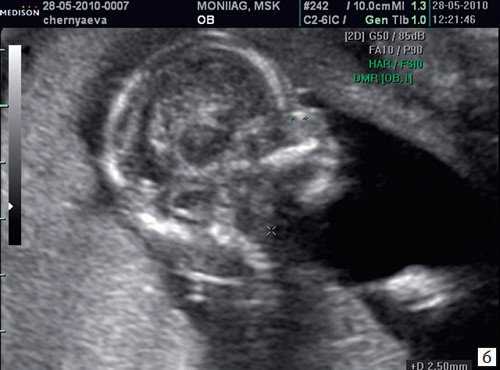

Копчико-теменной размер плода (КТР) для проведения скрининга I триместра должен быть в пределах 45-84 мм. Для оценки носовой кости в I триместре беременности необходимо соблюдать строгие условия. Это адекватное увеличение (на снимке должны быть только голова и верхняя часть грудной клетки), среднесагиттальный скан (должны быть визуализированы эхогенный кончик носа, небный отросток верхней челюсти, диэнцефалон), нос представлен тремя "К" (кончик носа, кожа, кость). Кожные покровы и кости носа визуализируются в виде знака "равенства", нос параллелен датчику.

Если все критерии соблюдены, то на уровне носа плода должны быть видны три четко различимые линии: верхняя линия представляет собой кожу, книзу от нее визуализируется более толстая и более эхогенная, чем кожа носовая кость. Третья линия, визуализируемая кпереди от носовой кости и на более высоком уровне, чем кожа - это кончик носа (рис. 1).

Рис. 1. Нормальная носовая кость.

Считается, что носовая кость нормальна, когда она по своей структуре более эхогенна, чем надлежащая кожа и патологична, если она не видна (аплазия) (рис. 2) или ее длина меньше нормы (гипоплазия) (рис. 3). В случае одинаковой или меньшей эхогенности носовой кости чем кожи носовая кость считается патологической (рис. 4).

а) Носовая кость в 12 нед и 2 дня длиной 1,4 мм (меньше нижней границы нормы).

б) Носовая кость 2,1 мм в 14 нед у плода с синдромом Дауна.